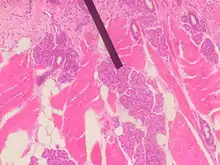

صورة مجهرية لغدة فون-إبنر في الإنسان.

غدّة فون-إبنر، أو غدة إبنر أو الغدد الذوقية، هي غدد خارجية الإفراز توجد في الفم. تعتبر تلك الغدد غدد لعابية مصلية تقع بجوار الخنادق المحيطة بالحليمات الكأسية والحليمات الورقية مباشرة أمام الثلث الخلفي من اللسان، أمام الثلم الإنتهائي.

تفرز غدد فون-إبنر إنزيم الليباز اللساني،[1] بادئةً عملية التحلل الدهني في الفم. تفرز تلك الغدد إفرازها المصلي في قاعدة الخنادق الموجودة حول الحليمات الكأسية والحليمات الورقية. تقوم تلك الإفرازات بغسل وإزالة أي مواد من الخنادق لكي تمكن "حلمات التذوق" من الاستجابة السريعة للمحفزات المتغيرة.